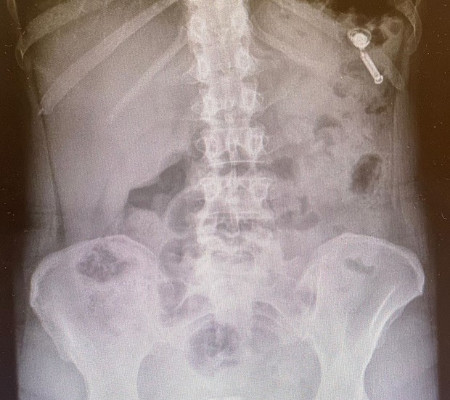

Mas nessa segunda-feira (23.12) ela surpreendeu seus mais de 100 mil seguidores com uma história inusitada. Com uma foto do raio-X de seu tórax, ela contou que engoliu acidentalmente um de seus fones de ouvido da marca AirPod (produzidos pela Apple). "Feliz natal pra você que teve a proeza de engolir um fone de ouvido remoto. PS: a paciente passa bem e tudo indica que da privada não passa", escreveu ela.